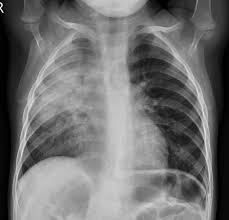

Esta distinción biológica se refleja en los patrones clínicos típicos y atípicos. La neumonía bacteriana típica suele presentarse de forma súbita con fiebre alta, tos productiva y signos de consolidación alveolar. Por otro lado, la neumonía atípica, muy frecuente en adolescentes, se caracteriza por un inicio gradual, fiebre leve, dolor de cabeza y una tos seca persistente. Desde el punto de vista de la fisiopatología, la consolidación alveolar se confirma clínicamente mediante la auscultación de ruidos respiratorios bronquiales o tubulares y matidez a la percusión. La causa principal de la baja saturación de oxígeno es el desequilibrio entre ventilación y perfusión, conocido como efecto shunt, donde los alvéolos ocupados por exudado impiden el intercambio gaseoso efectivo mientras el flujo sanguíneo continúa.

En cuanto al diagnóstico e investigaciones, en casos de neumonía bacteriana leve y no complicada el proceso es fundamentalmente clínico. Las guías internacionales actuales recomiendan no realizar radiografías de tórax de rutina en pacientes estables, ya que esto no cambia la conducta médica y expone innecesariamente al niño a la radiación. La oximetría de pulso se mantiene como el estándar de oro para detectar la hipoxemia de forma no invasiva, considerando que una saturación inferior al 92 % requiere el inicio de oxígeno suplementario. En escenarios de casos graves o con apariencia tóxica, es imperativo obtener hemocultivos antes de administrar la dosis de antibiótico para intentar identificar el patógeno específico.